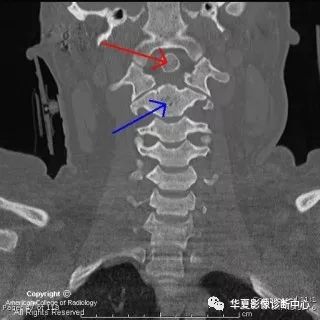

【影像图片】CT MPR图像

【影像表现】:The coronal CT neck image in Figure 1 shows a small, round os odontoideum (red arrow) separated from the body of C2 (blue arrow) by a wide radiolucent gap. It has smooth and uniform cortical margins.冠状位CT显示一个小圆形的齿突(红箭),与颈2椎体分离(蓝箭),皮质边缘均匀平滑。